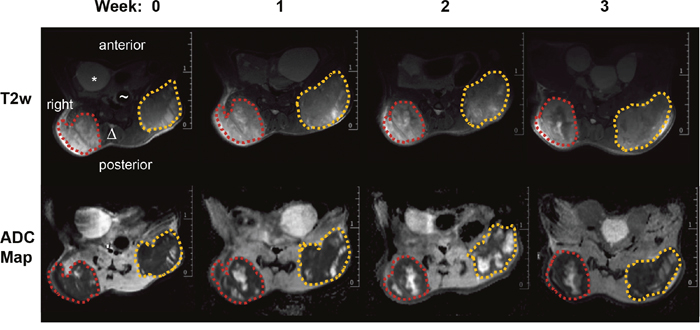

Over the entire period of investigation, the tumors were accessible to external measurement by caliper and clearly detectable both by MRI and PET/CT imaging with 18F-FDG (Figure 1 and 2). Both imaging techniques indicated a heterogeneous structure of the tumor with vital tumor tissue in the peripheral zone and central necrotic areas. Haematoxylin and eosin (H&E) staining of the tumor tissue at the time of necropsy confirmed these findings (Figure 3A). Cells expressing the proliferation marker Ki-67 [17] (Figure 3B) were exclusively found in the peripheral regions of the tumors. Apoptotic cells were in general very scarce and almost exclusively found in the transition zone between vital and necrotic areas (Figure 4).

Figure 1: MR images of a mouse from the control group. top row: representative T2 weighted transversal images (red dotted line: right tumor volume; orange dotted line: left tumor volume, * bladder, Δ spine, ~ gut); bottom row: ADC-maps derived from DWI for four different time points (0, 1, 2 and 3 weeks) showing heterogeneous tumors with solid tumor mass (dark areas represent tissue with low ADC values) and pervading necrotic/cystic areas (bright areas with high ADC values).